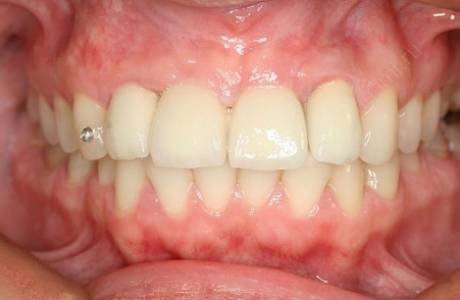

После лечения

По окончании срока приживления были установлены 4 металлокемарические коронки, которые идеально восстановили эстетику улыбки и вернули пациентке возможность улыбаться.